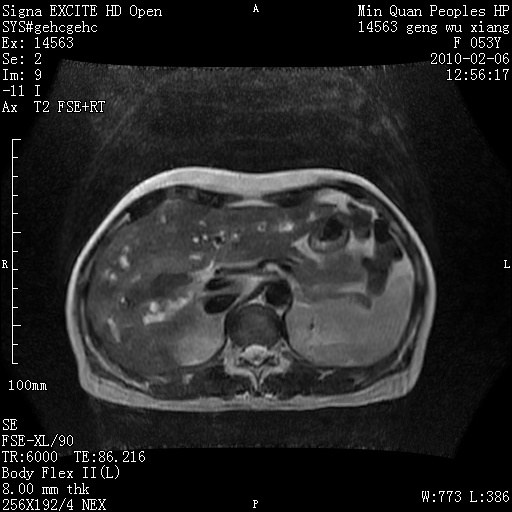

标题: MRI2762:胆道梗阻原因?

f,53y,全身黄染多日。

高位胆道梗阻 胆管癌可能性大

支持 高位胆道梗阻 胆管癌可能性大。